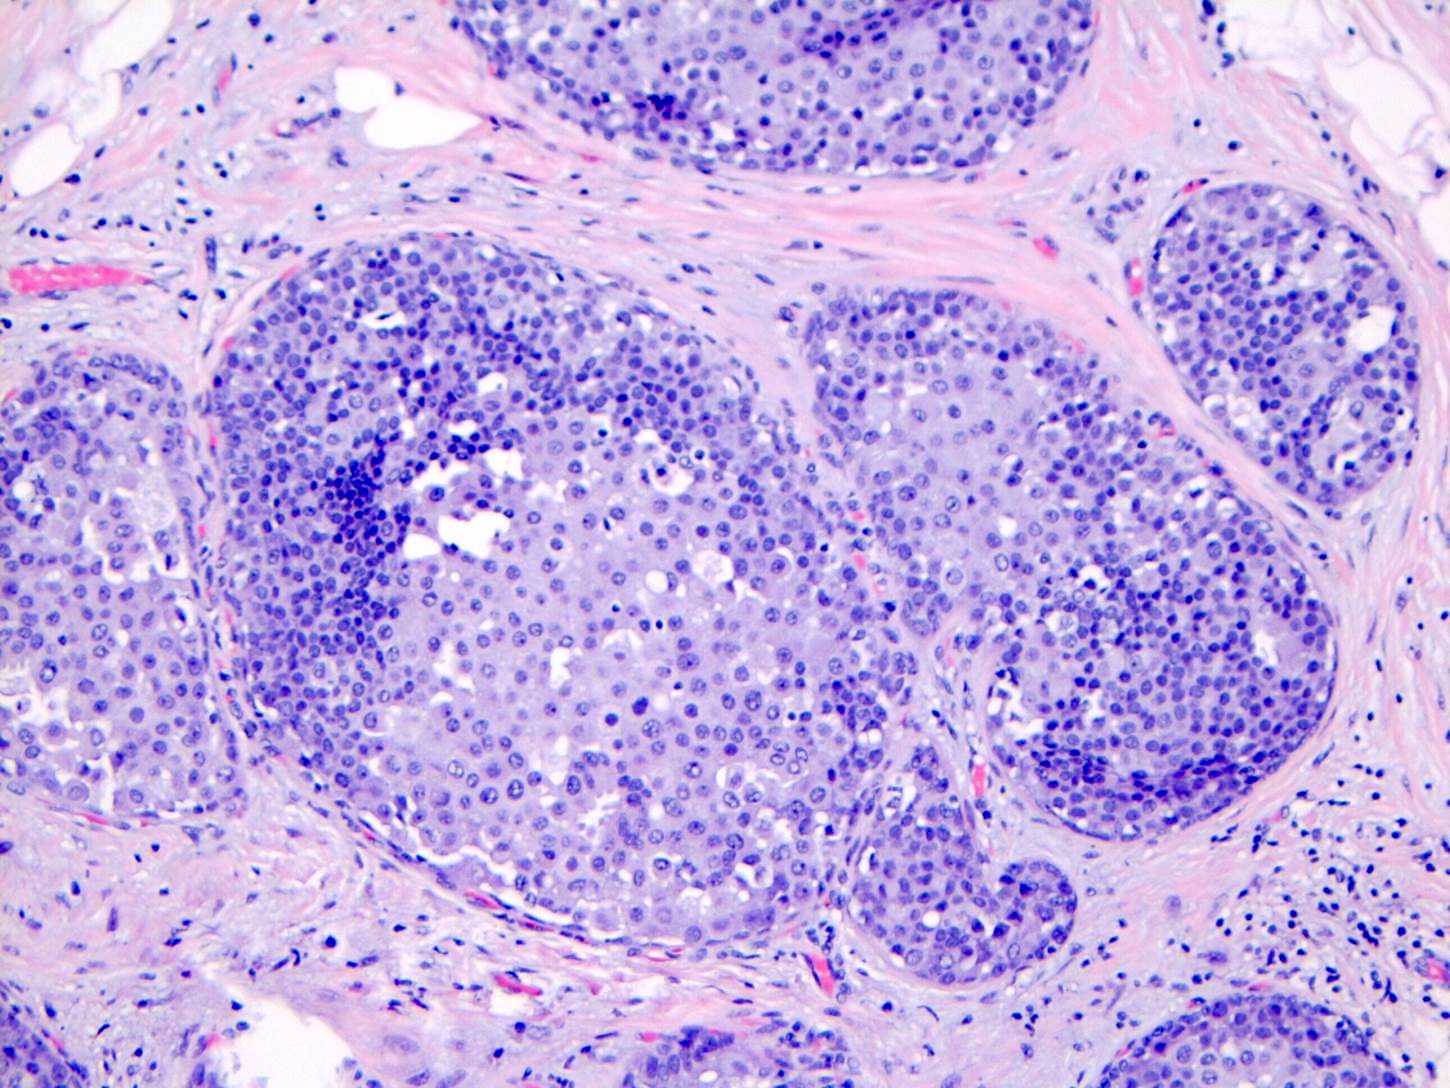

Microscopic (histologic) description

- LCIS involves the terminal duct lobular unit (TDLU), filling and distending acini

- > 50% of the acini in a TDLU must be filled and expanded to qualify as LCIS; otherwise, called atypical lobular neoplasia

- Lobular distention is defined as the presence of ≥ 8 cells in the cross sectional diameter of an acinus

- Involved lobules may be compared with uninvolved lobules to estimate the degree of distension

- LCIS most often involves lobules but may also grow along the basement membrane of ducts (i.e., pagetoid spread)

- Pagetoid spread in ducts is the characteristic growth of cells between luminal and myoepithelial layers of a duct without destroying ductal epithelium or filling up ductal lumina

- Often makes the ducts appear convoluted; this is called a cloverleaf pattern

- Classic LCIS cells are monomorphic, evenly spaced, loosely cohesive and do not show polarization or gland formation

- 2 types of cells are described:

- Type A: nuclei are small to slightly enlarged (1 - 1.5x size of lymphocyte) with uniform round nuclei and inconspicuous nucleoli

- Type B: nuclei larger (2x size of lymphocyte), more abundant cytoplasm and more prominent nucleoli

- Type A and B cells can coexist in the same lesion

- Cytoplasm of LCIS cells is typically pale to lightly eosinophilic with indistinct cell borders

- In almost all cases of LCIS, at least some cells contain intracytoplasmic vacuoles or lumina, which may contain an eosinophilic globule; this feature is not specific to LCIS

- Vacuoles may be subtle such that special histochemical stains for mucin are required in order to demonstrate; alternatively, they may be large enough to push the nucleus against the cell membrane and produce signet ring cell forms

- Outer layer of myoepithelial cells is retained in the acini and ducts involved but it may be attenuated

- Classic LCIS does not show significant nuclear pleomorphism or mitosis

- Classic LCIS may rarely display single cell apoptosis or minute foci of necrosis but typically does not show comedo type necrosis

Microscopic (histologic) images

Contributed by Anna Biernacka, M.D., Ph.D.